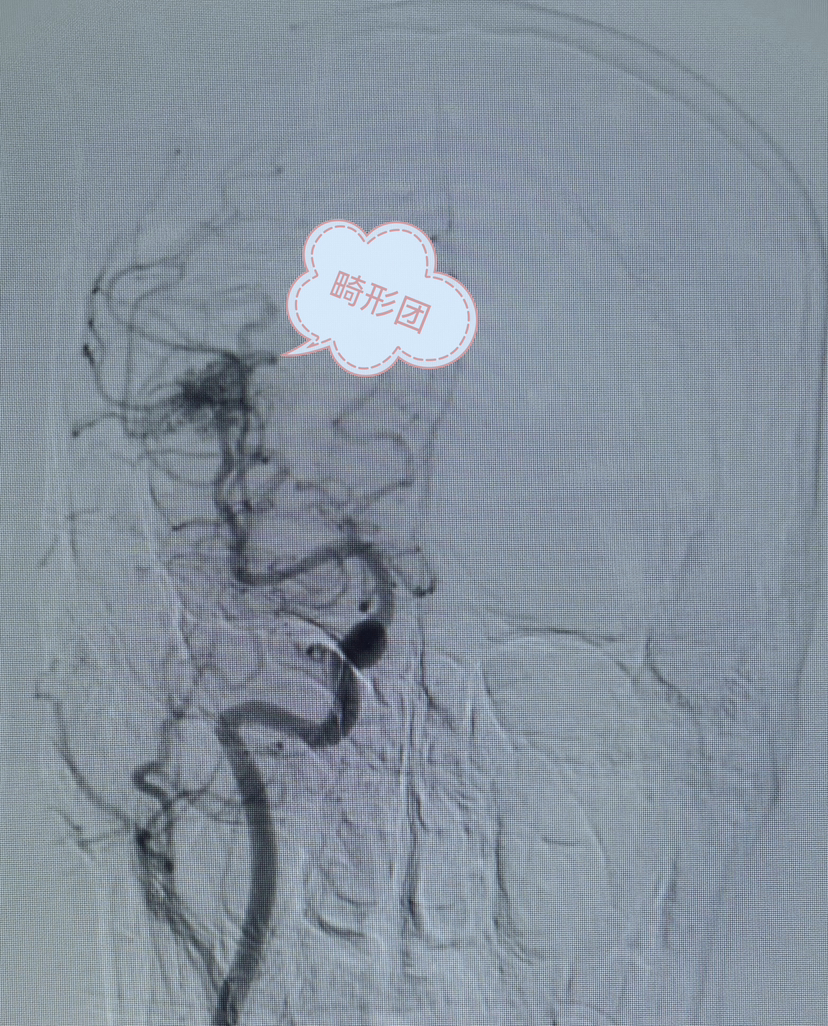

DSA正位